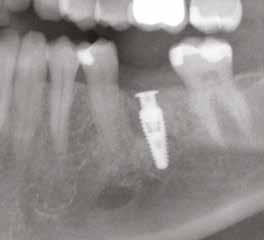

A korai harmicas éveiben járó hölgy rendelőnkbe érkezésének oka a jobb felső nagymetsző fog bizonytalan érzkenysége, elmondása alapján gyermekkorában trauma érte a felső frontrégiót. A frakturált klinikai koronákat kompozittöméssel helyreállították, egyéb kezelést akkor nem tartottak szükségesnek. Az utóbbi hónapokban tapasztalt érzékenység miatt kereste fel rendelőnket. A klinikai vizsgálat (1. és 2. kép) és a CBCT felvétel (3. kép) alapján diagnosztizált külső gyökérreszorpció megoldására a fog eltávolítását, implantátum

bukkális 1. kép: Kiindulási állapot, 2020. január. 3. kép: Kiindulási CBCT felvétel. 2. kép: Kiindulási állapot a palatinális oldal felől.